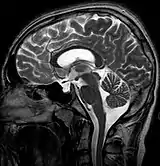

![]() | |

| MRI of Empty Sella | |